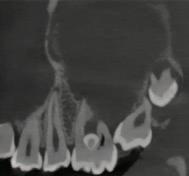

1. What condition is affecting the first permanent molar in Figure 1?

2. What is the estimated global prevalence of the condition according to the European Academy of Paediatric Dentistry (EAPD) Best Clinical Practice Guidelines?

3. List the main aetiological factors that have been linked to this condition.

4. What signs and symptoms of the condition influence clinical management of affected teeth?

FIGURE 1: What condition is affecting this first permanent molar?